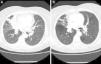

Fue derivada a nuestro servicio en 2011 ante tos seca crónica, apreciándose en la radiografía de tórax un engrosamiento hiliar derecho y atelectasia-condensación parcial del bronquio segmentario anterior del lóbulo superior derecho (LSD). Dichos hallazgos fueron confirmados con TC torácica, encontrándose también bronquiectasias en LSD y una adenopatía paratraqueal derecha de 2cm (fig. 1A). Ante sospecha de carcinoma bronquial se realizó broncoscopia que mostró un muñón de lobectomía del lóbulo medio sin signos de neoformación y una extensa mancha de color negro en la entrada del bronquio del lóbulo superior izquierdo, de la que solo se pudo biopsiar una única muestra de tejido por sangrado importante, y que contenía mucosa bronquial con macrófagos en la lámina propia y pigmento citoplasmático negro, sin datos de malignidad. El resto de los bronquios segmentarios de ambos pulmones fueron impracticables por estenosis, especialmente manifiesta en los colindantes a la mancha hacia el culmen y la língula. En el broncoaspirado se aisló Mycobacterium tuberculosis resistente a isoniazida.

La paciente recibió tratamiento durante 6 meses con etambutol, piracinamida y rifampicina, tras el que se observó en la TC de control resolución parcial del infiltrado en el bronquio segmentario anterior del LSD con normalización del tamaño de la adenopatía (fig. 1B). El aspecto endoscópico no experimentó cambios a pesar del tratamiento. En nuevas muestras de broncoaspirado y lavado broncoalveolar se confirmó la erradicación del bacilo de Koch.